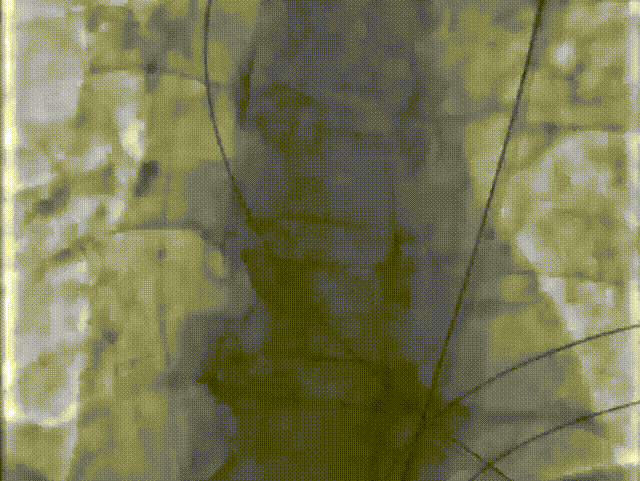

手术关键步骤

B. 不前扩,输送系统一步到位

C. 应用交界贴合技术调整人工瓣膜,到安全梢固定位置,定位好,不需要回收,直接释放

D. 瓣膜释放后造影